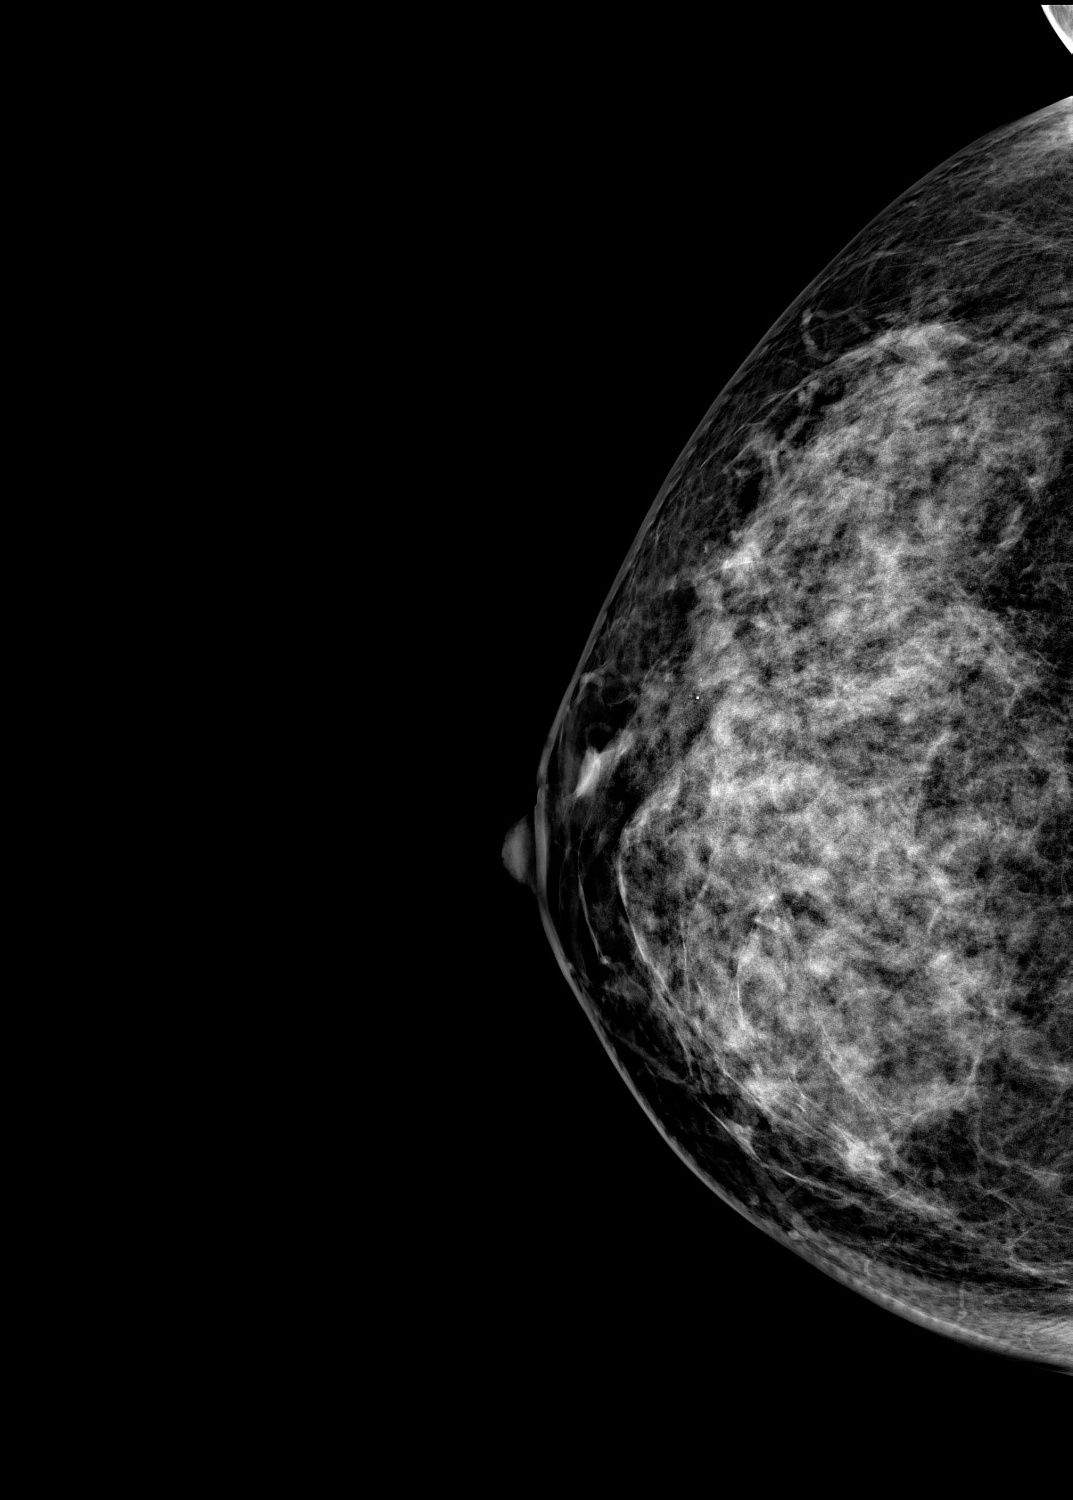

Маммограф выявляет опухоли молочной железы размером от 1-2 мм, которые не определяются при осмотре врача и самообследовании. На снимках хорошо различимы мельчайшие скопления солей кальция (от 87 мкм), тяжистые и другие перестройки тканей, характерные для рака груди 1-2 стадии. Высокую информативность, диагностическую ценность изображений обеспечивает цифровой детектор с самым чувствительным в мире сцинтиллятором. На снимках также определяются воспалительные процессы, кисты и даже небольшие повреждения.

Универсальный размер детектора делает обследование женщин с большим размером груди проще и безопаснее. Функция съемки молочных желез с имплантами позволяет обследовать эту категорию пациенток. На снимках хорошо различимы и ткани груди, и грудные эндопротезы.

Рентгеновский маммограф BRESTIGE EXPERT INDIRECT оснащен чувствительным сенсором непрямого преобразования на основе аморфного кремния. Цифровой детектор этого типа отличается надежностью и обеспечивает высокое качество изображения. Детальная «картинка» получается благодаря активной матрице, содержащей 2816 × 3584 пикселей, и хорошей квантовой эффективности (до 50%). На снимках ясно различимы даже небольшие изменения в структуре тканей и малоконтрастные образования.

Полноформатный детектор облегчает и ускоряет обследование женщин с большими молочными железами, а также делает его безопаснее. Пациенткам с грудью до пятого размера включительно для полноценного исследования достаточно 4 снимков: по 2 для каждой молочной железы. Аппараты, укомплектованные детектором меньшего размера, требуют 8 экспозиций.

Режим позволяет проводить маммографию у пациенток с грудными эндопротезами. На снимках хорошо видны ткани груди. Снимки отражают состояние импланта, в том числе его серьезные повреждения.